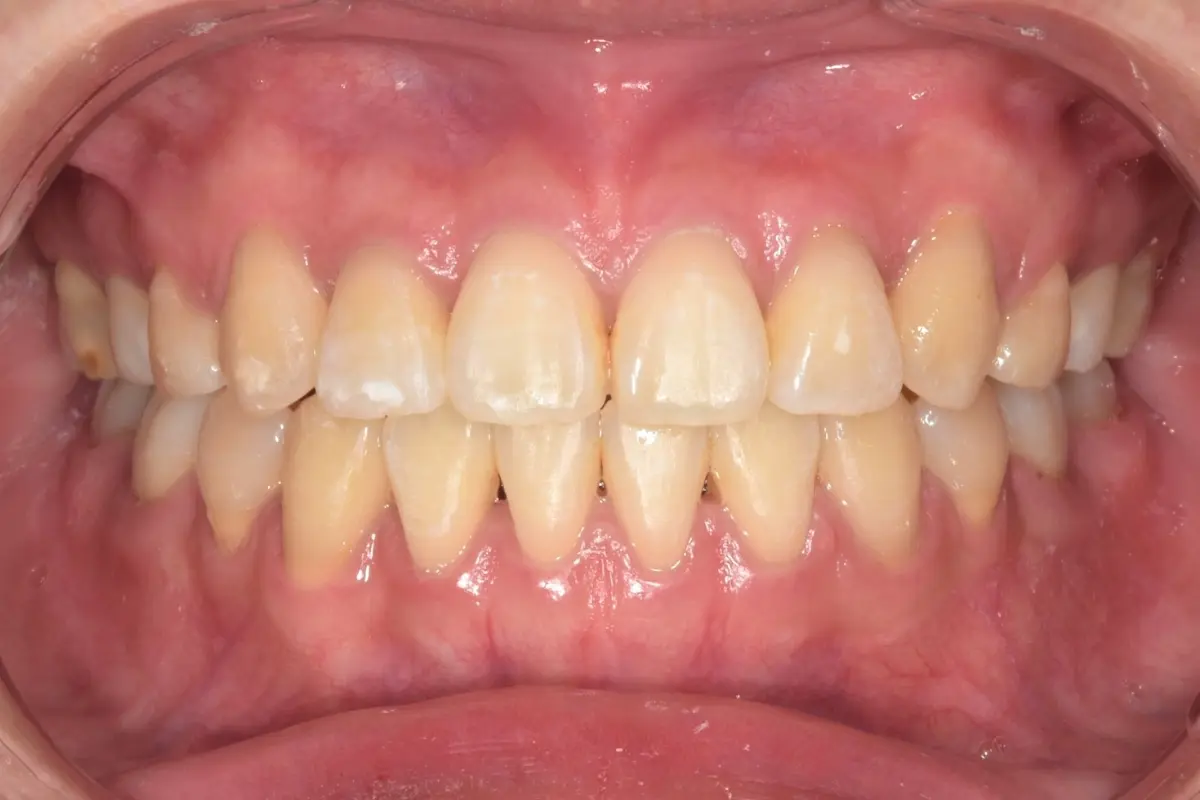

• 術前 44

術後 42

仿生美學樹脂

主治醫師

• 陳暐文

治療時間

單次療程

主訴

門牙有縫、牙齒形狀偏方,笑起來不夠自然